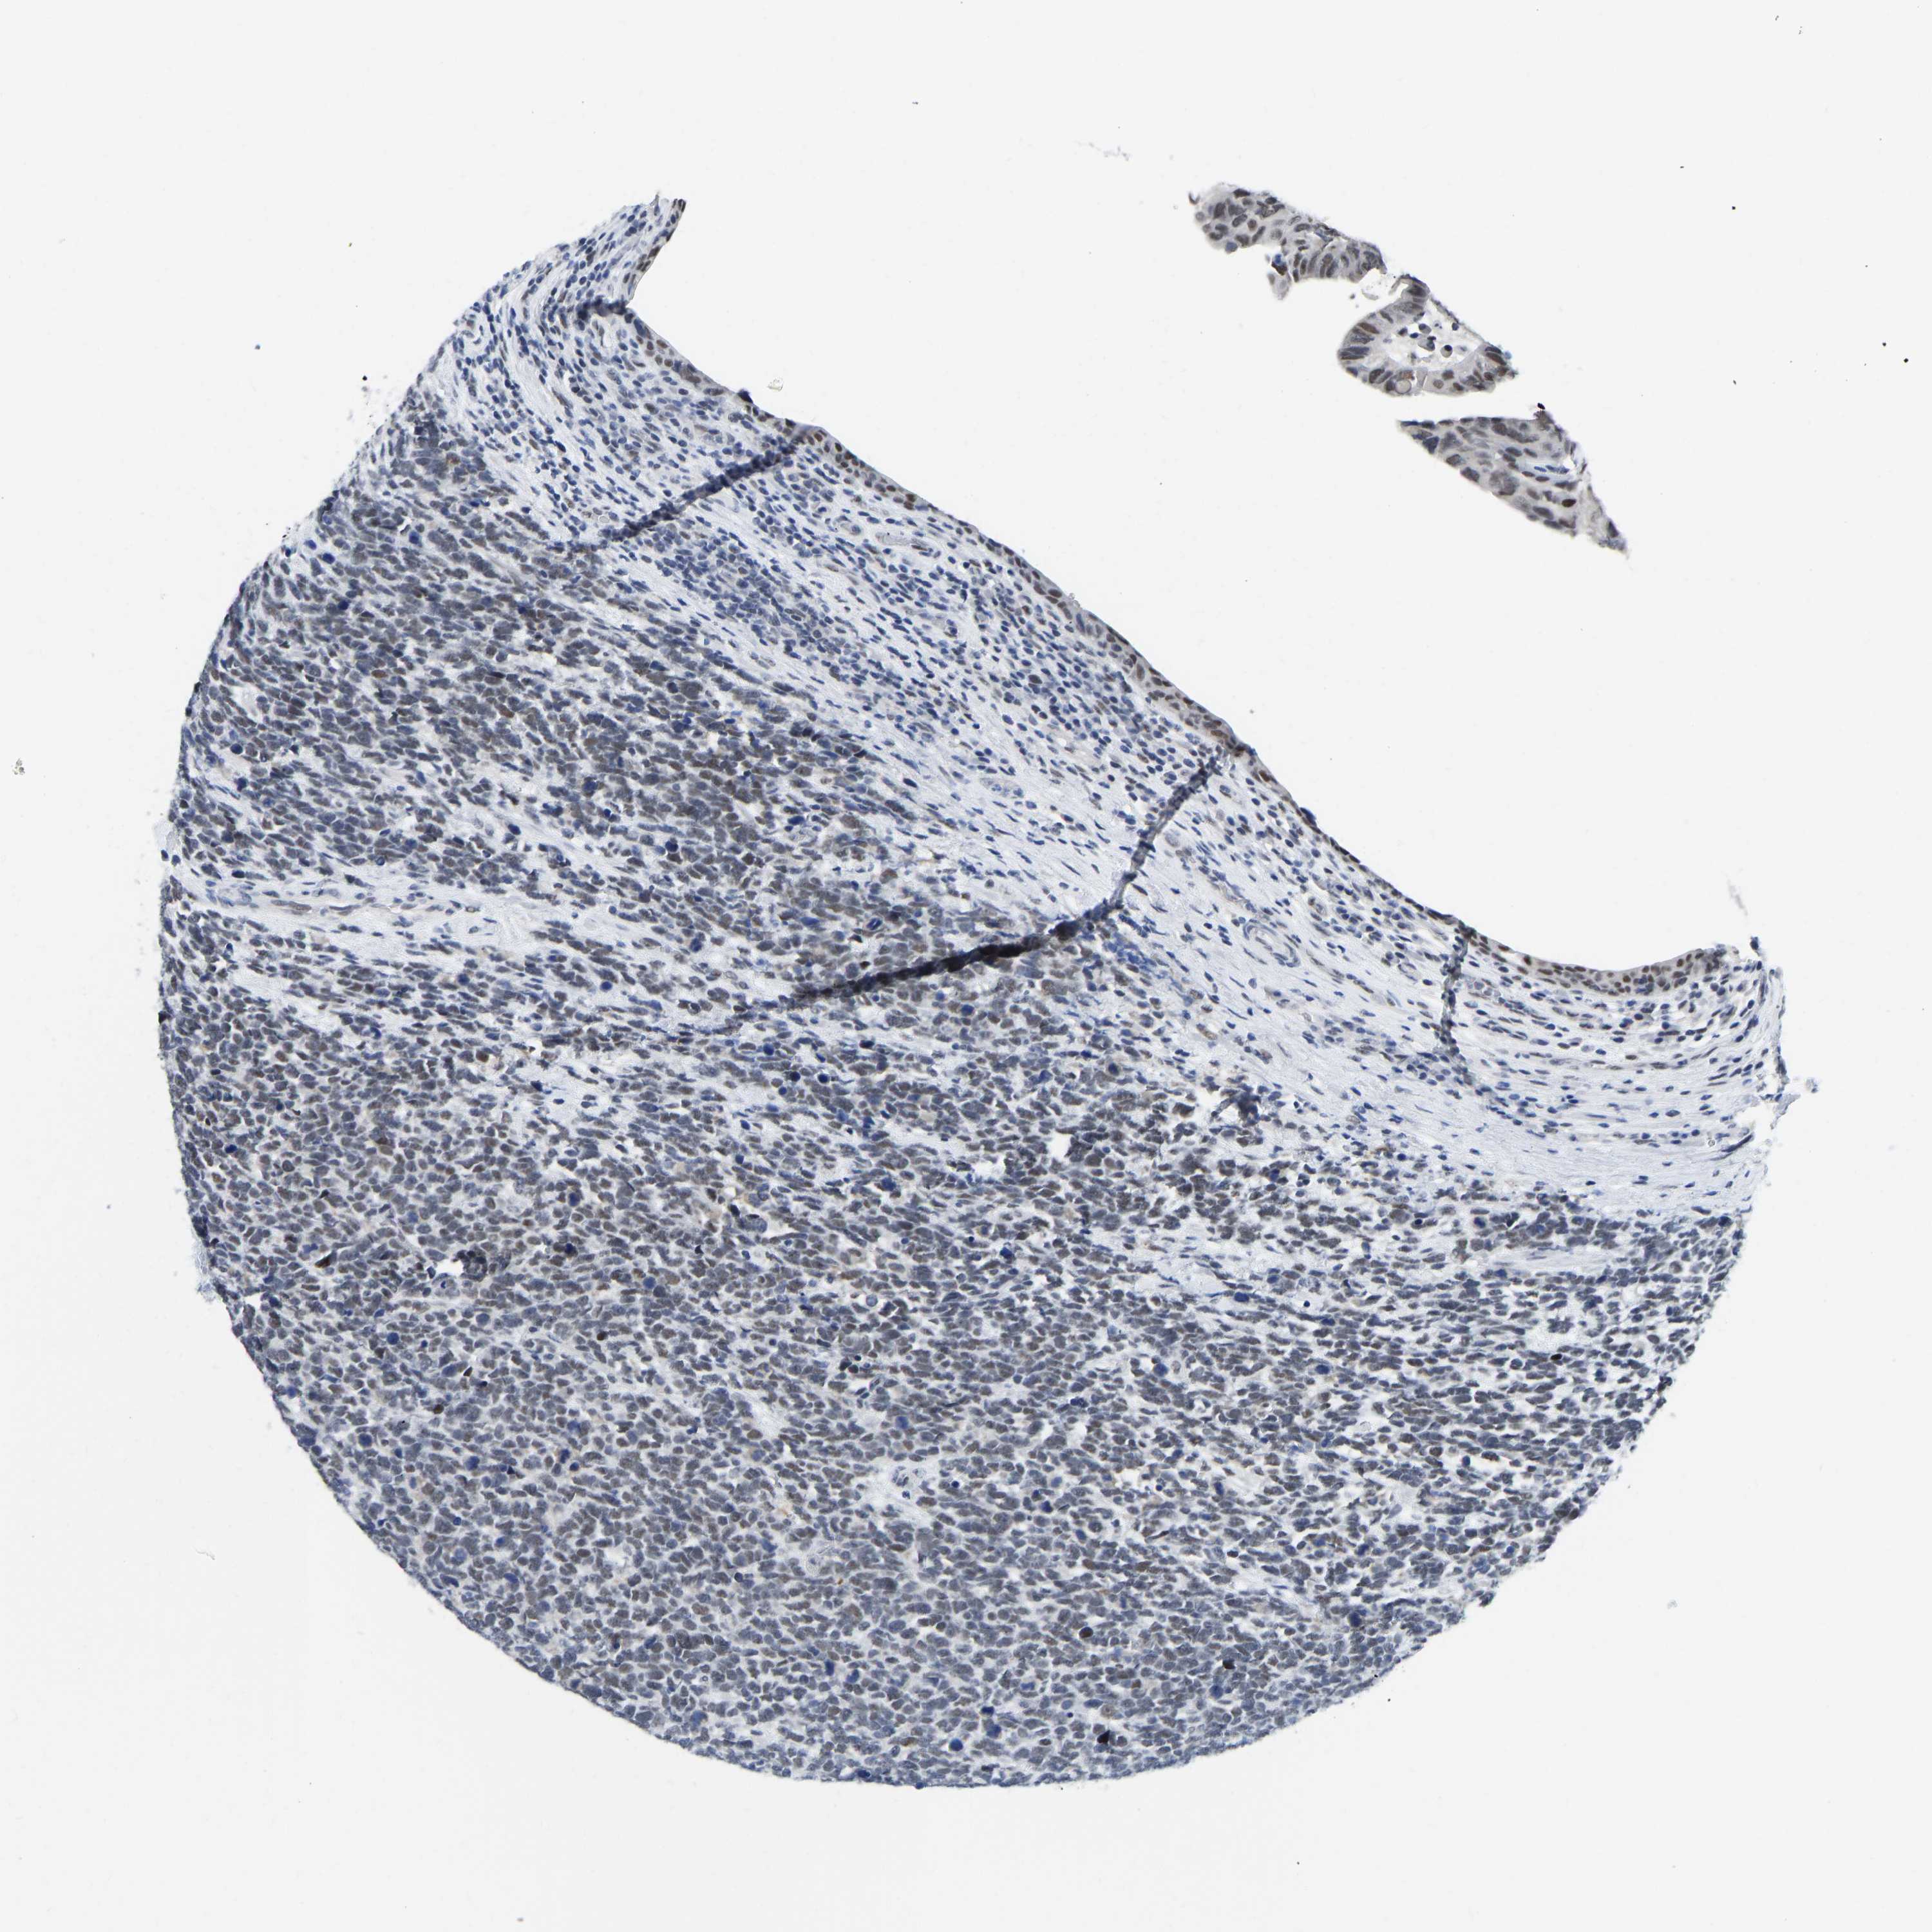

UROTHELIAL CANCER - Protein expressioni

A mouse-over function shows sample information and annotation data. Click on an image to view it in a full screen mode. Samples can be filtered based on level of antibody staining by selecting one or several of the following categories: high, medium, low and not detected. The assay and annotation is described here.

Note that samples used for immunohistochemistry by the Human Protein Atlas do not correspond to samples in the TCGA dataset.

Antibody stainingi

Antibody staining in the annotated cell types in the current human tissue is reported as not detected, low, medium, or high, based on conventional immunohistochemistry profiling in selected tissues. This score is based on the combination of the staining intensity and fraction of stained cells.

Each image is clickable and will lead to virtual microscopy that enables deeper exploration of all samples and also displays staining intensity scores, fraction scores and subcellular localization as well as patient and tissue information for each sample.

Antibody CAB019416

Staining

High

Medium

Low

Not detected

Intensity

Strong

Moderate

Weak

Negative

Quantity

>75%

75%-25%

<25%

None

Location

Urothelial carcinoma, Low grade

Urothelial carcinoma, High grade